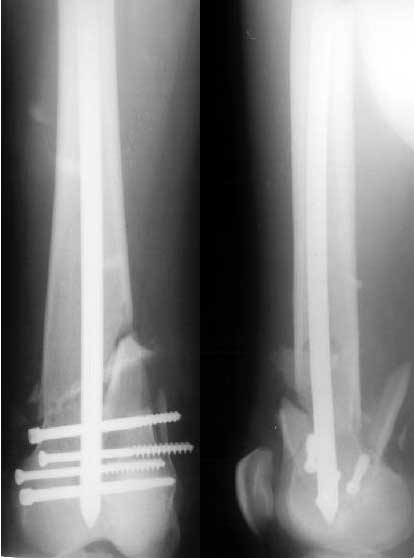

A mail 27 y.o. was operated Apr 2, 2002 2 weeks after injury (impact by a heavy construction) - he had open Gustilo II distal femoral fracture (image 1). Antegrade closed nailing by UFN 11 mm was performed (image 2). The second leg was amputated above the knee at the initial hosptial. To provide early weight bearing 6 mm locking screws were used so sll static holes were drilled accordingly. 2 months after the surgery he started to load the limb, before only knee ROM excersises were perfomed. The cyclic loadings produces stress riser and the nail was broken 10 days ago (image 3). Now he admitted to us again. It is the first case of such complication we meet. Now i plan to push the broken fragment distally and then perfrom retrograde nailing by UFN (distal femoral nails are not available in my settings). If the attempt would be too complicated we'll change to XF. Or plating is a good option here?

But anyway all these could be empty reasoning, looking at your x-rays the your reconstruction was superb. And usually we are happy and relaxed if we have such post-op x-ray, they heal in 99% of the cases. Bad luck here...

THX for the valuable suggestions about the subject. Actually we don't have a set for broken implant retrieval through the antegrade incision. So as we planned the piece was pushed out distally and the nail was replaced by the same but inserted from below. I locked it statically at the moment. Comments are welcome.